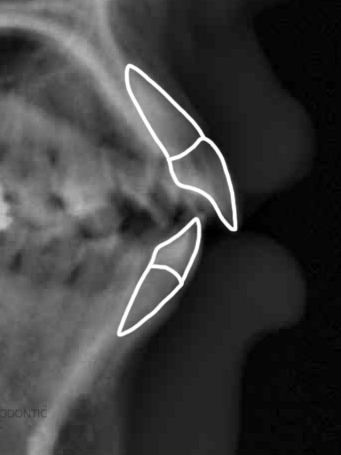

1. 치아 X 선촬영

치아 X-선 촬영은 필름을 입안에 두고 천체 치아상태 , 치주조직, 치열궁, 구저부 파악하는데 이용되는 방법이다. 대부분 파노라마 X선 촬영을 하여 1장의 필름상에 상악골 및 하악골 특히 전악의 치아가 동시에 촬영가능한 X-선촬영법이다.